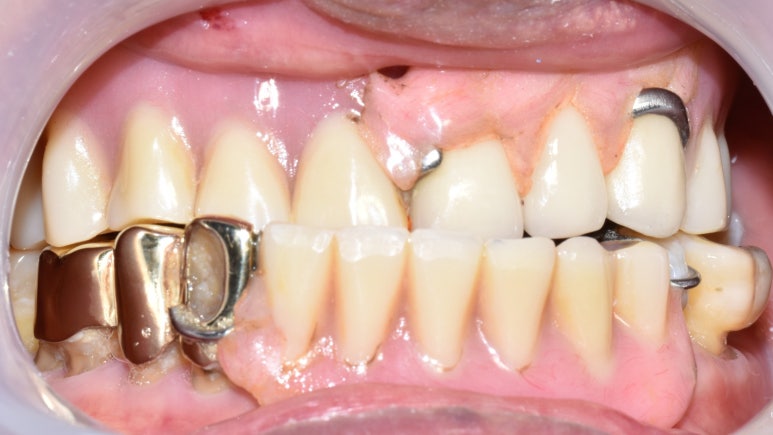

- 위의 틀니와 아래 어금니 임플란트를 5년쓰시다가

어금니 임플란트가 너무 편하고 뺐다 꼈다하는 틀니가 귀찮다고 하셔서 위 전체 임플란트

-

원래 치아상태 ->2. 위 틀니, 하악어금니 임플란트 ->3. 상악도 전체 임플란트로.